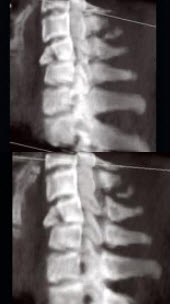

A.胸部

男,68岁,从2米高的平台坠落后颈部疼痛6小时,结合影像学检查,最可能的诊断是()

A.脊椎结核

B.椎体压缩性骨折

C.脊椎转移瘤

D.化脓性脊柱炎

E.强直性脊柱炎